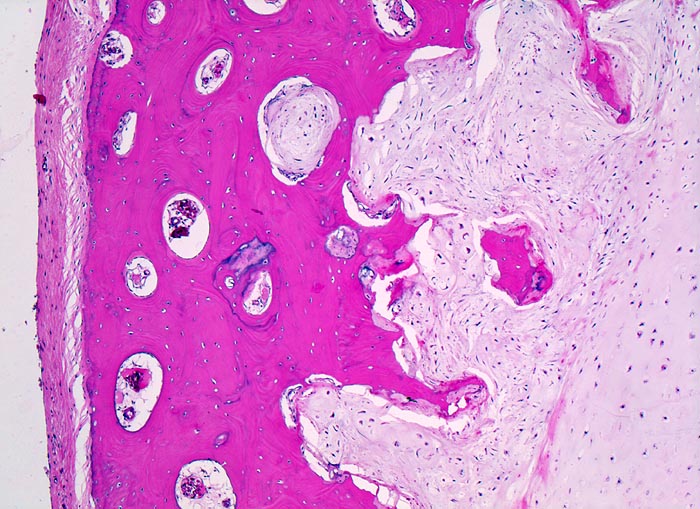

• Zellarmer lobulierter Knorpeltumor.

• Destruktive Tumorinfiltration des spongiösen und kortikalen Knochens.

• Der maligne Knorpel mit reichlich heller chondroider Matrix gleicht nicht neoplastischem hyalinem Knorpelgewebe.

• Im Vergleich zu normalem Knorpel leicht erhöhte Zellularität.

• In Höhlen liegende Tumorzellen mit hyperchromatischen, leicht vergrösserten Kernen.